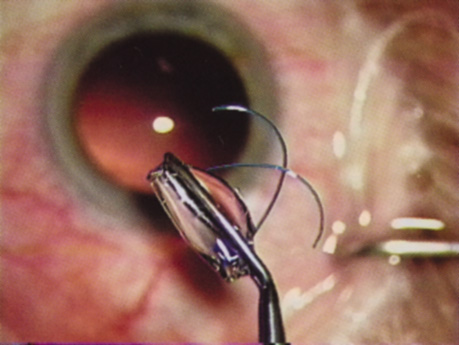

Despite numerous incision choices, one key factor is recommended for all cataract incisions: The incision should be self-sealing. A self-sealing incision decreases the risk of catastrophic expulsive hemorrhage if significant positive pressure develops for any reason. If positive pressure develops at any time during the procedure, simple removal of the instrument should prevent expulsion of the intraocular contents. Additionally, if properly placed and constructed, a self-sealing incision obviates the need for a suture, thereby avoiding suture distortion of the wound and induced astigmatism. Closure of the incision, regardless of incision type, should ensure that intraocular pressure or external pressure at the posterior lip of the incision, or elsewhere, will not cause wound leak. If leakage occurs, then stromal hydration or suture placement may be necessary. Whenever placing a suture across a cataract incision, the ocular tension should approximate normal pressure before tightening the suture. Doing so helps prevent the surgeon from overtightening the suture, which would induce astigmatism. ANTERIOR CAPSULOTOMY One of the most beneficial techniques developed over the last decade is capsulorrhexis. A continuous curvilinear anterior capsular opening helps prevent intraoperative and postoperative complications. With capsulorrhexis, mechanical strength of the capsular opening is superior to that in a can-opener capsulotomy; thus, a tear to the posterior capsule with subsequent vitreous loss is much less likely.96 Capsulorrhexis allows for nuclear manipulation with less risk of posterior capsule rupture. Cortex removal is made easier as well, because it becomes easier to differentiate cortical material from anterior capsule. Should a posterior capsular tear occur, sulcus fixation is more likely attainable with the presence of a clearly visible residual anterior capsular rim. Placement of both IOL haptics into the capsular bag is more certain with capsulorrhexis because the surgeon can more easily visualize the haptics gliding beneath the anterior capsular rim. Capsulorrhexis can be performed with a cystitome, capsulorrhexis forceps, or combination-type instruments. Regardless of which instrument is used, several principles can help the surgeon successfully complete capsulorrhexis. It is important to maintain the anterior chamber, because making the chamber shallow increases tension on the zonules and causes the tear to run peripherally. The authors recommend the use of a viscoelastic agent for maintaining chamber depth and, of course, for endothelial protection. Therefore, if the tear begins to run peripherally, the surgeon should redeepen the anterior chamber before attempting to redirect the tear. Additionally, folding the capsule margin can aid the surgeon in redirecting the tear more accurately (Fig. 10).